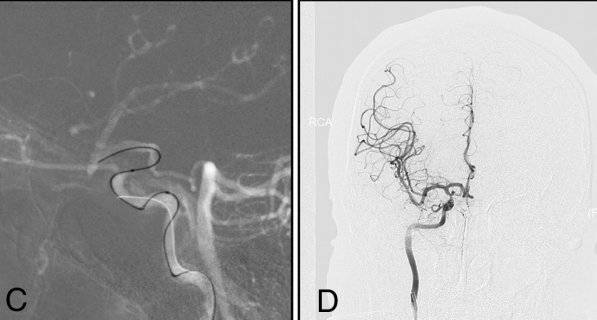

对于典型明显存在PcomA或AcomA的I型和II型病变,我们使用了双侧血管同时注入造影剂建立路图明确阻塞节段(图2和3)。微导丝(Synchro,Stryker;Transend EX 014/205软头,Stryker)与微导管(Echelon-10,Medtronic;Excelsior SL-10,Stryker)结合使用,小心地通过闭塞节段。如果反复尝试,微导丝和微导管不能通过闭塞节段进入远端血管真腔,则停止手术。如果成功引导微导丝穿过闭塞节段,则微导管造影确认微导管在闭塞远端血管真腔内。随后,将长交换微导丝(Transend ES 014/300 Floppy;Stryker)放置在适当的位置锚定,收回微导管。沿微导丝送入2-2.5mm的Gateway(Stryker)球囊至闭塞节段球扩成形。根据球囊扩张后闭塞血管近端和远端的直径以及长度,根据术者的熟悉度释放自膨支架(Wingspan,Stryker;Neuroform EZ,Stryker;或Enterprise,Codman&Shurtleff)。

图3. 男性患者,右侧肢体无力30天,言语不利10天。A和B,DSA显示左侧颈内动脉颅内段闭塞,闭塞长度>10mm,通过AcomA(II型)向右侧颈内动脉颅内远端ICA代偿供血;C,在双路图的指导下,微导丝与微导管结合穿过闭塞节段;D,成功再通。